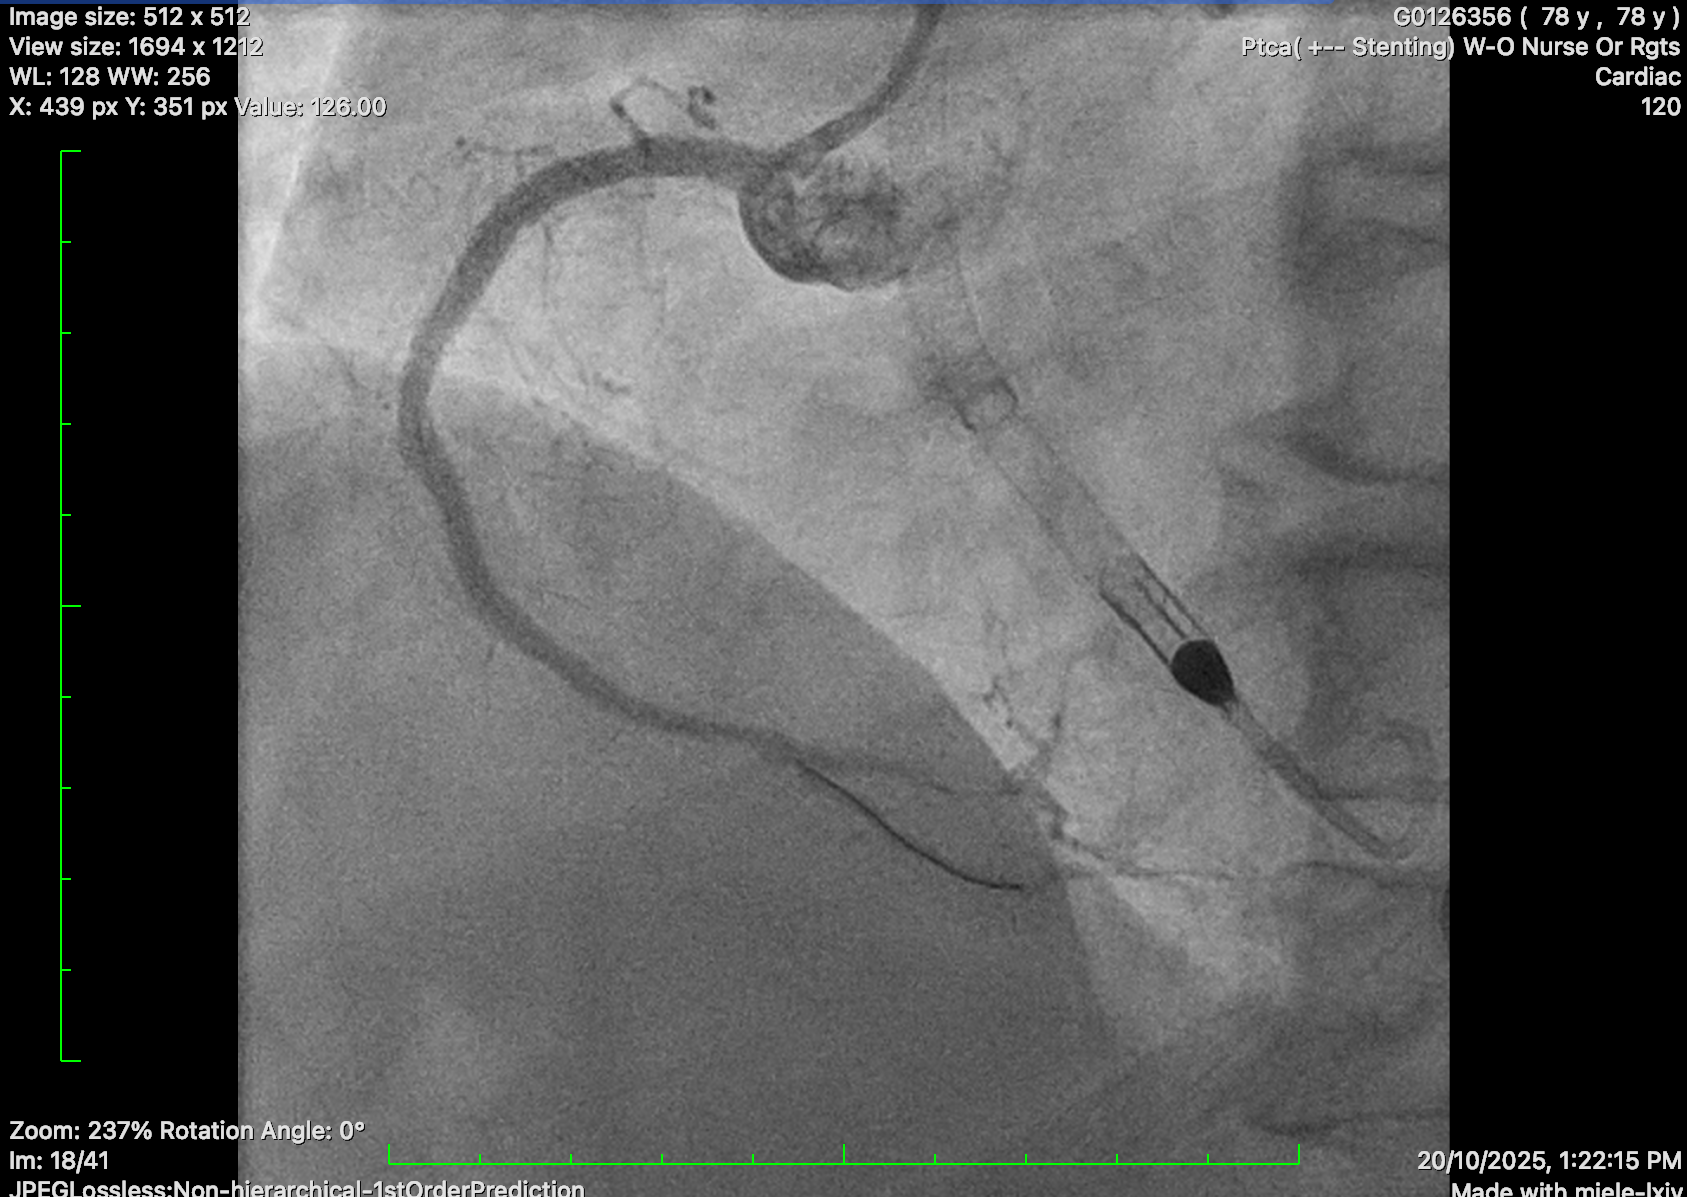

Diagnostic coronary angiogram was performed, showing distal left main disease and ostial LAD subtotal occlusion with antegrade flow, diffuse severe disease over proximal to mid LAD. Mid-LCx showed severe stenosis. RCA was dominant, with mRCA severe disease followed by subtotal occlusion with antegrade collateral to distal RCA and retrograde collateral to septal branches of LAD and diffuse severe disease at PL branch.

Impella CP inserted due to underlying poor LVEF and intention for rotational atherectomy in the left main.

PCI to LCA: EBU 3.0 7 Fr guide catheter. Successful wiring to distal LAD with workhorse wire. Unable to cross SC 1.0 balloon. Exchanged for Rotawire Extra Floppy. 1.25mm burr for rotational atherectomy with significant decelerations. Still failed to deliver SC 1.0 and 1.5 balloon. Upsized to 1.5mm Rotaburr. Further dilated with SC 1.5 and 2.0 balloon, then shockwave with 2.5 balloon and further predilatation with NC balloon. DES 2.25/30, 3.0/18 and 3.5/24 deployed. Post dilatation with NC 4.0 and 3.5 balloon.